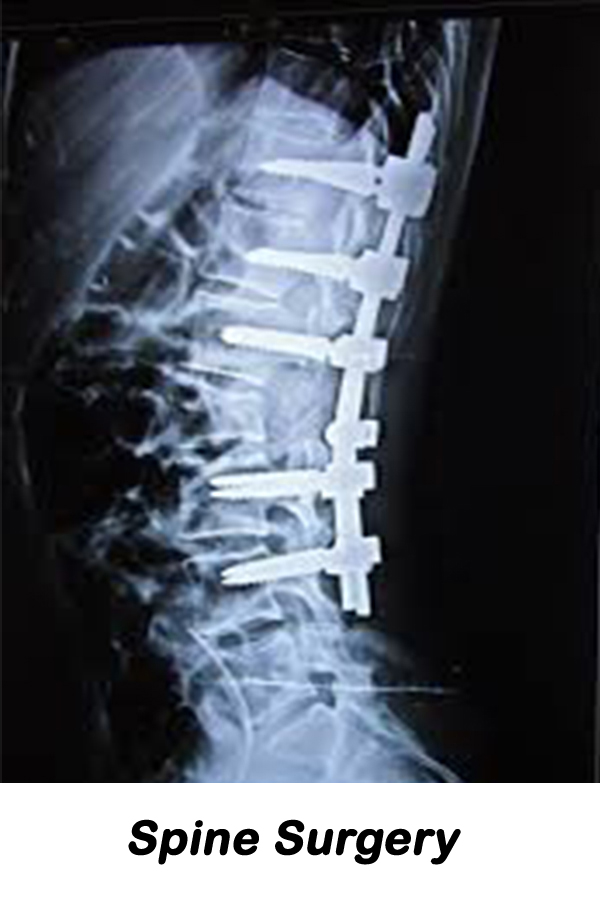

Shreerang Hospital is orthopaedic specialty hospital and is designed specifically for the orthopedic patient. Such a specialized facility and team of experts means we have the utmost in experience and understanding of the needs of orthopaedic patients meaning better outcomes, increased patient satisfaction and a reduced risk of infection or complications. Our goal is to provide you with the ultimate patient experience and excellent outcomes when undergoing orthopaedic surgery. Your care, comfort & peace of mind is constantly our top priority from pre-admission through your surgery & stay at our hospital.

Be the best place for orthopaedic & surgical, Provide quality and accessible orthopaedic & surgical services with the latest technology & equipments.

Our objective to maintain high standards of orthopaedic & surgical treatment, care and surgery. The main objective of the hospital is to offer high quality and more prominent patient care.